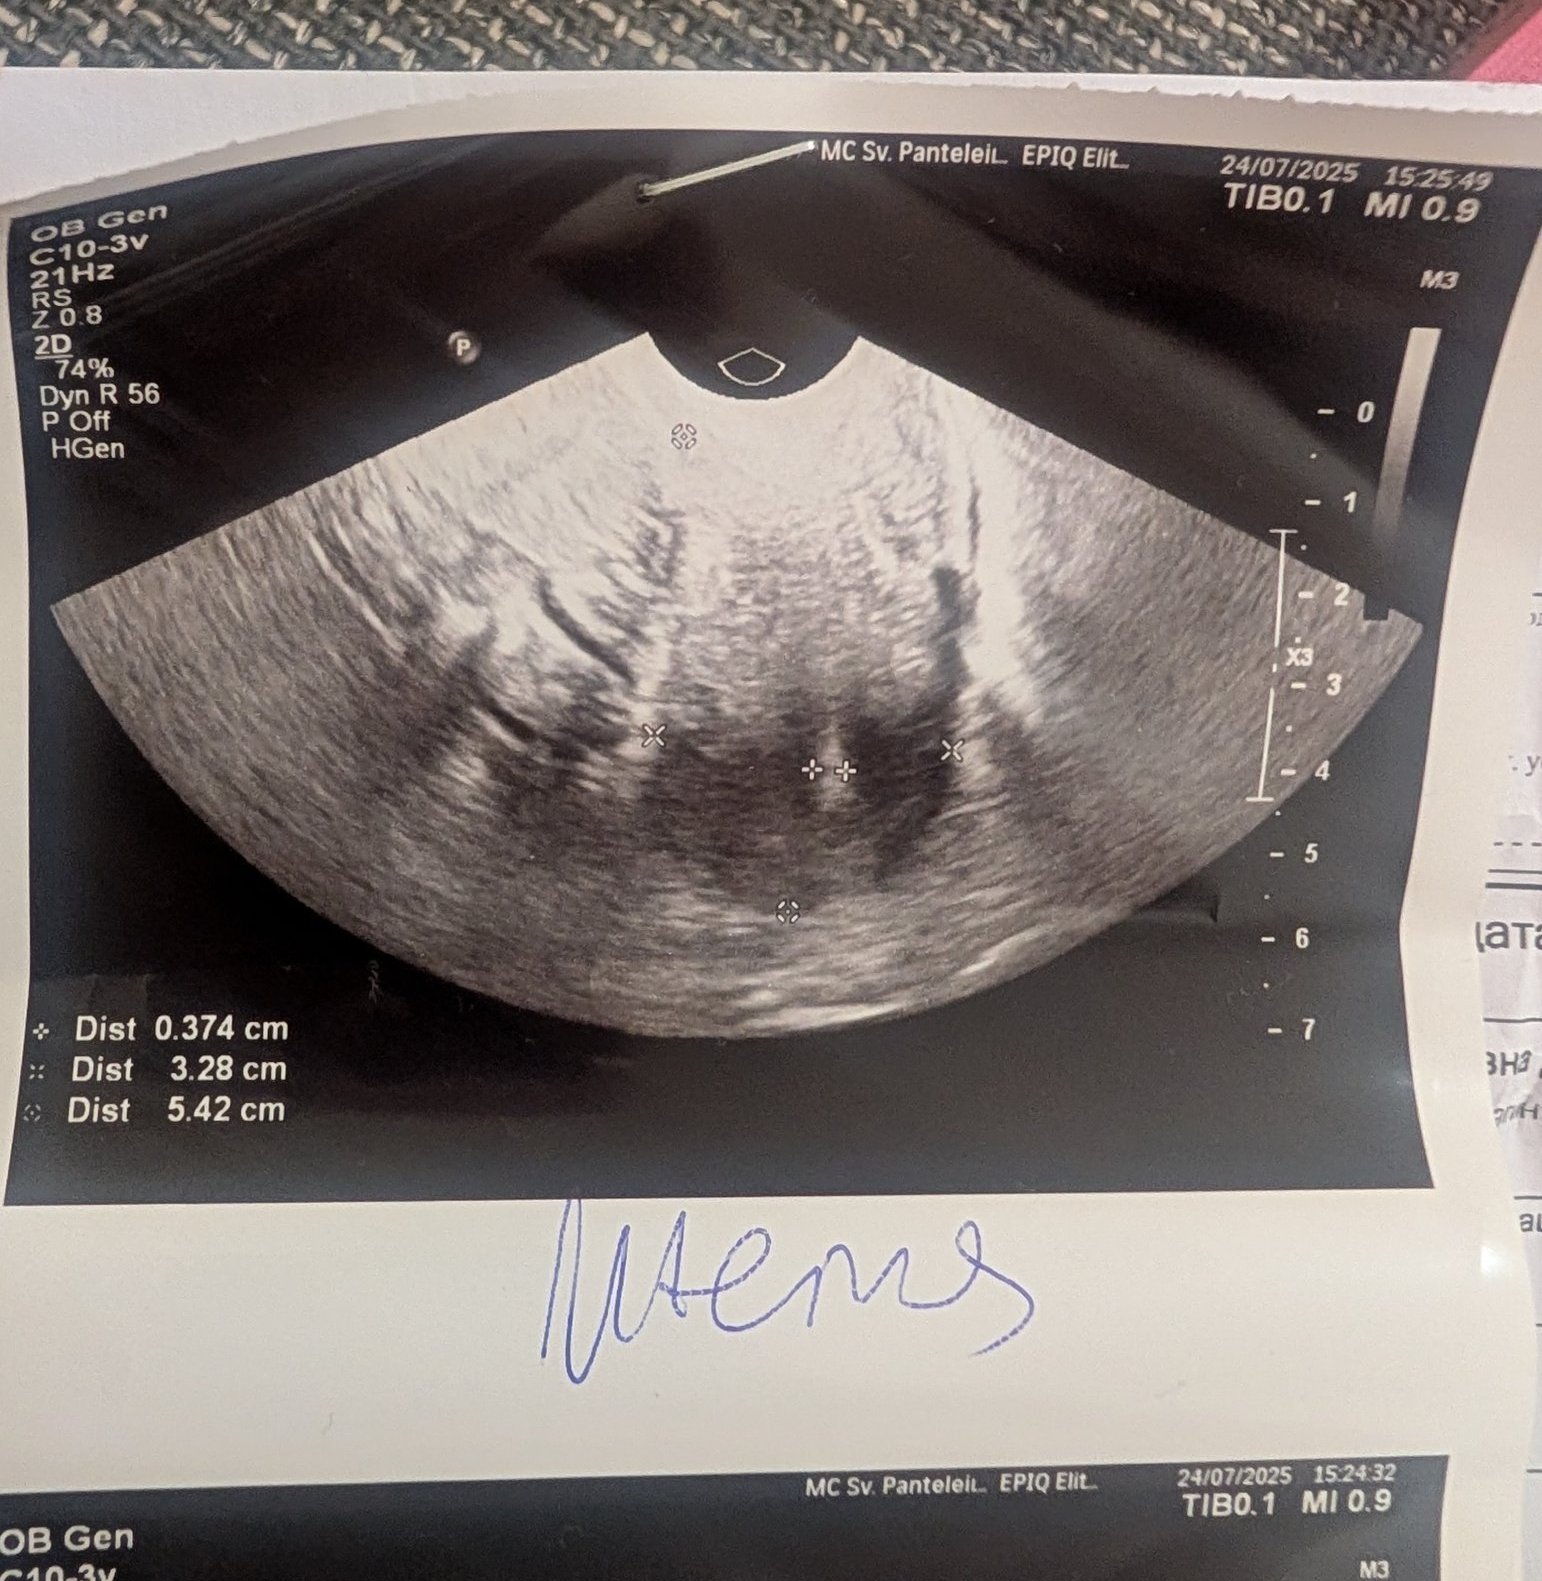

Какво представлява изображението от ехографията на 5-седмична и 2-дневна бременност?